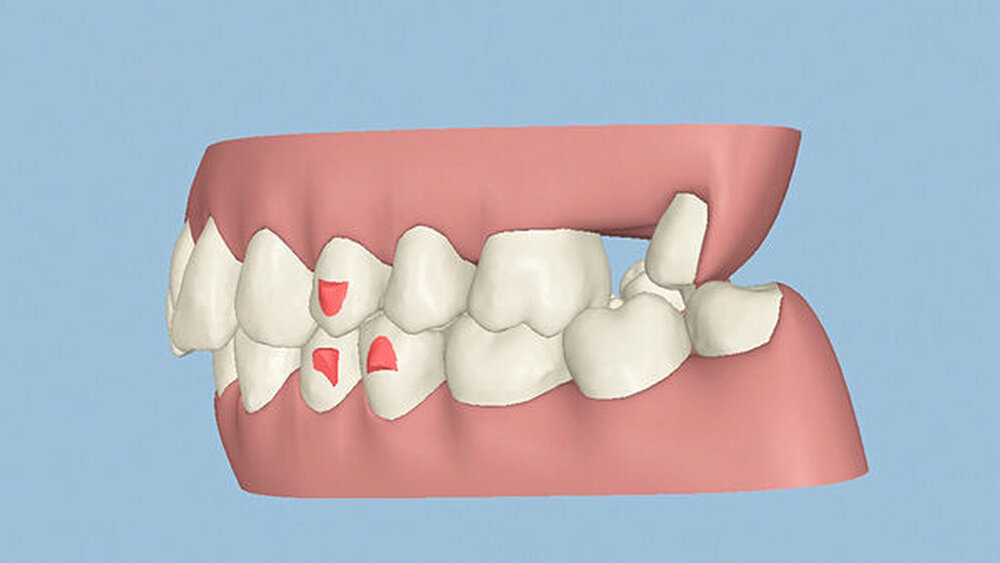

Röntgenologisch stellte sich im Orthopantomogramm der bereits intraoral ersichtliche horizontale und vertikale Knochenabbau mit Attachmentverlust an einzelnen Zähnen dar. Die Erhaltungswürdigkeit einzelner Zähne war aufgrund des starken Knochenverlustes beziehungsweise der Beeinträchtigung des Halteapparates als kritisch zu beurteilen.

Zudem wurde die Diagnose einer Parodontitis gestellt, die eine Rücküberweisung an den Hauszahnarzt erforderlich machte (Abbildung 2).